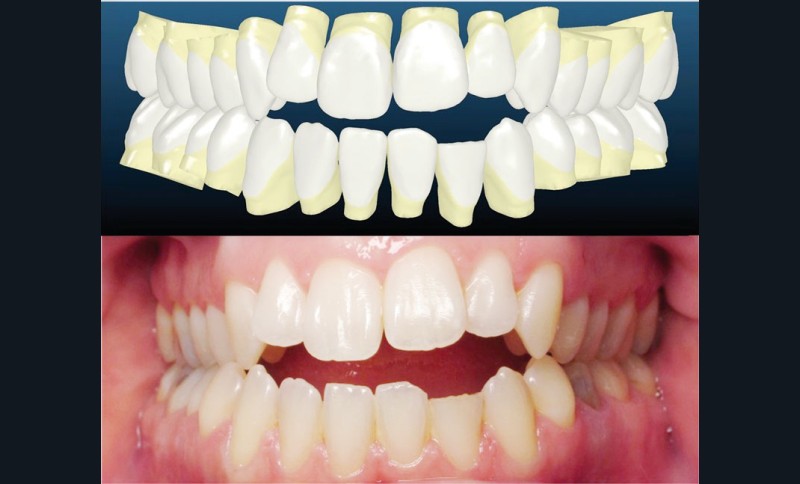

Le set up Insignia

Les empreintes ont été réalisées en sillcone wash technique et adressées au laboratoire Insignia. Actuellement, nous réalisons ces empreintes à l’aide de la caméra intra-orale Lythos et la fiche patient est initialement créée sur la caméra. Le transfert des empreintes au laboratoire est immédiat et le risque d’erreurs considérablement réduit (fig. 4 à 6).